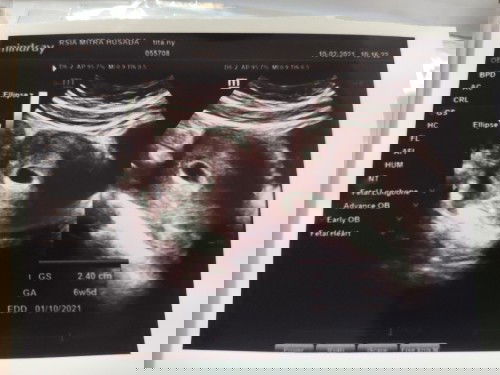

Asalamualaikum,slm sejahtera para Bunda,, bisakah sy brtanya adakah disini pengalamam Bunda yg usia kandungan 7minggu lebih namun belum terlihat janin nya? Karna,sy skg lg hamil 8minggu,namun saat USG pd usia kehamilan 7mggu tdk terdeteksi janin,hny kantong janin saja. Sy cemas ini mnjd BO/Blated Ovum. Apakah dsini ada Bunda yg bs berbagi info nya,, terimakasih .#seriusnanya #jangandibully